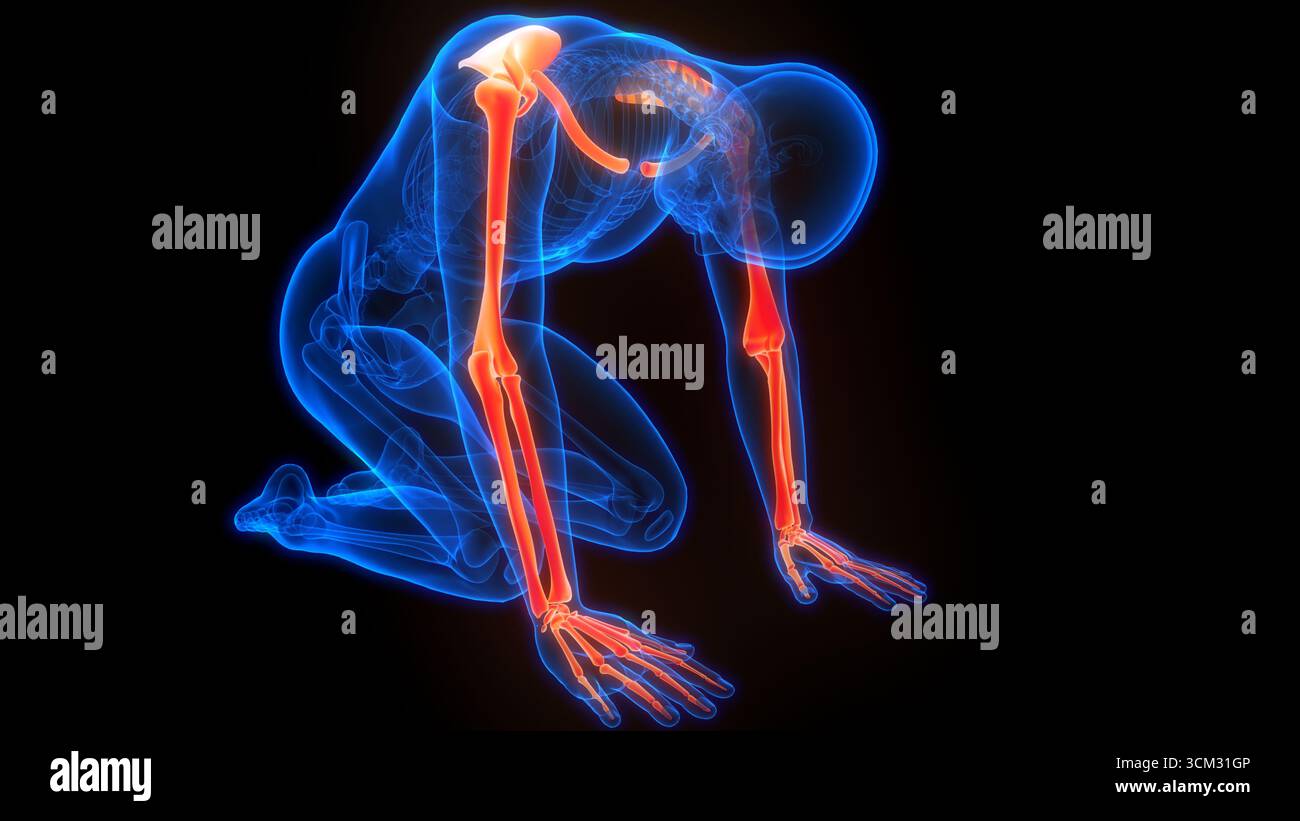

RF3CM31GP–3D-Illustrationskonzept der Anatomie der Knochengelenke der oberen Extremitäten des menschlichen Skelettsystems

RF3CM2YY5–3D-Illustrationskonzept der Anatomie der Knochengelenke der oberen Extremitäten des menschlichen Skelettsystems